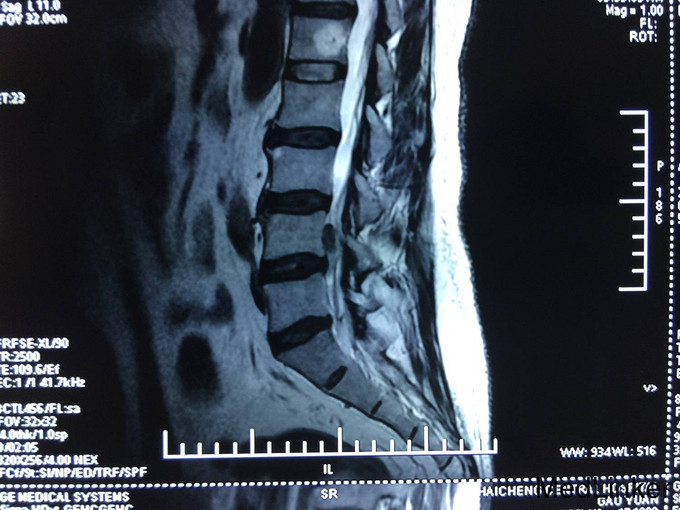

主诉:腰痛加重及左下肢疼痛1个月 现病史:患者自述腰痛10余年,休息及卧床缓解,不影响生活,未进行诊治。近一个月病情逐渐加重,腰部疼痛加重,出现左下肢麻木疼痛严重影响患者生活质量。今为求进一步治疗而来我院,我科以“腰椎间盘脱出症”为诊断收住院治疗。病来无发热,无头痛及头晕,无恶心,呕吐,无胸痛及呼吸困难,无腹胀及腹痛,饮食,睡眠较差,大小便未及异常。

专科查体:患者跛行入病房,腰椎正常生理曲线减小,腰部无明显压痛及叩击痛,髂腰肌肌力(L5,R5),股四头肌肌力(L5,R5),足趾背伸肌力(L5,R5),跖屈肌力(L5,R5),肌张力未及明显异常。直腿抬高试验(L,50°),加强试验阴性,健腿抬高试验阴性,PSR(L++,R++),ASR(L++,R++),Babinski'sign(L-,R-),双侧足背动脉搏动正常。

诊断 : 腰椎间盘脱出症,髓核游离 入院后完善检查,查无手术禁忌症后行腰椎后路椎板减压间盘切除椎间融合器椎弓根钉内固定术,术后患者左下肢疼痛缓解,术后支具保护下三天后拔除引流管后下地行走。